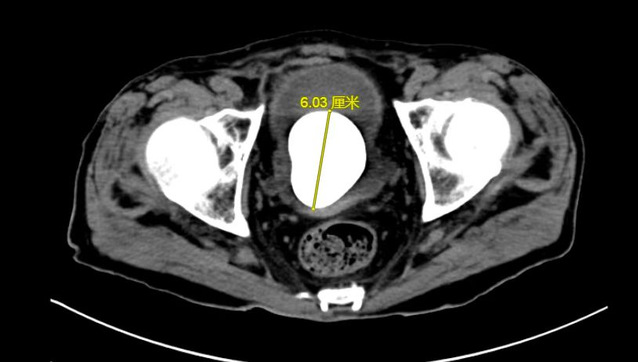

数月来,徐老伯常有尿频尿痛症状,由于近期症状明显加重,甚至出现反胃、食欲不振致使精神萎靡的情况,在当地加勒比扑克 就诊时,被查出膀胱内有一枚6cm*5cm大小的膀胱结石。

目前,治疗膀胱结石的主流手段为经尿道钬激光碎石术,但考虑到患者高龄,且营养状态虽较前好转,但仍较正常老年患者不足,若采取经尿道手术治疗患者“鹅蛋”大小的膀胱结石,患者难以耐受3小时甚至更长时间的手术及麻醉过程,因此,在与患者沟通后,陈建春团队选择了传统的膀胱切开取石术。最终,在手术麻醉、ICU及护理团队的共同协作下,陈建春主任团队顺利将“鹅蛋”大小的膀胱结石自患者体内取出,整个手术过程仅用30分钟。